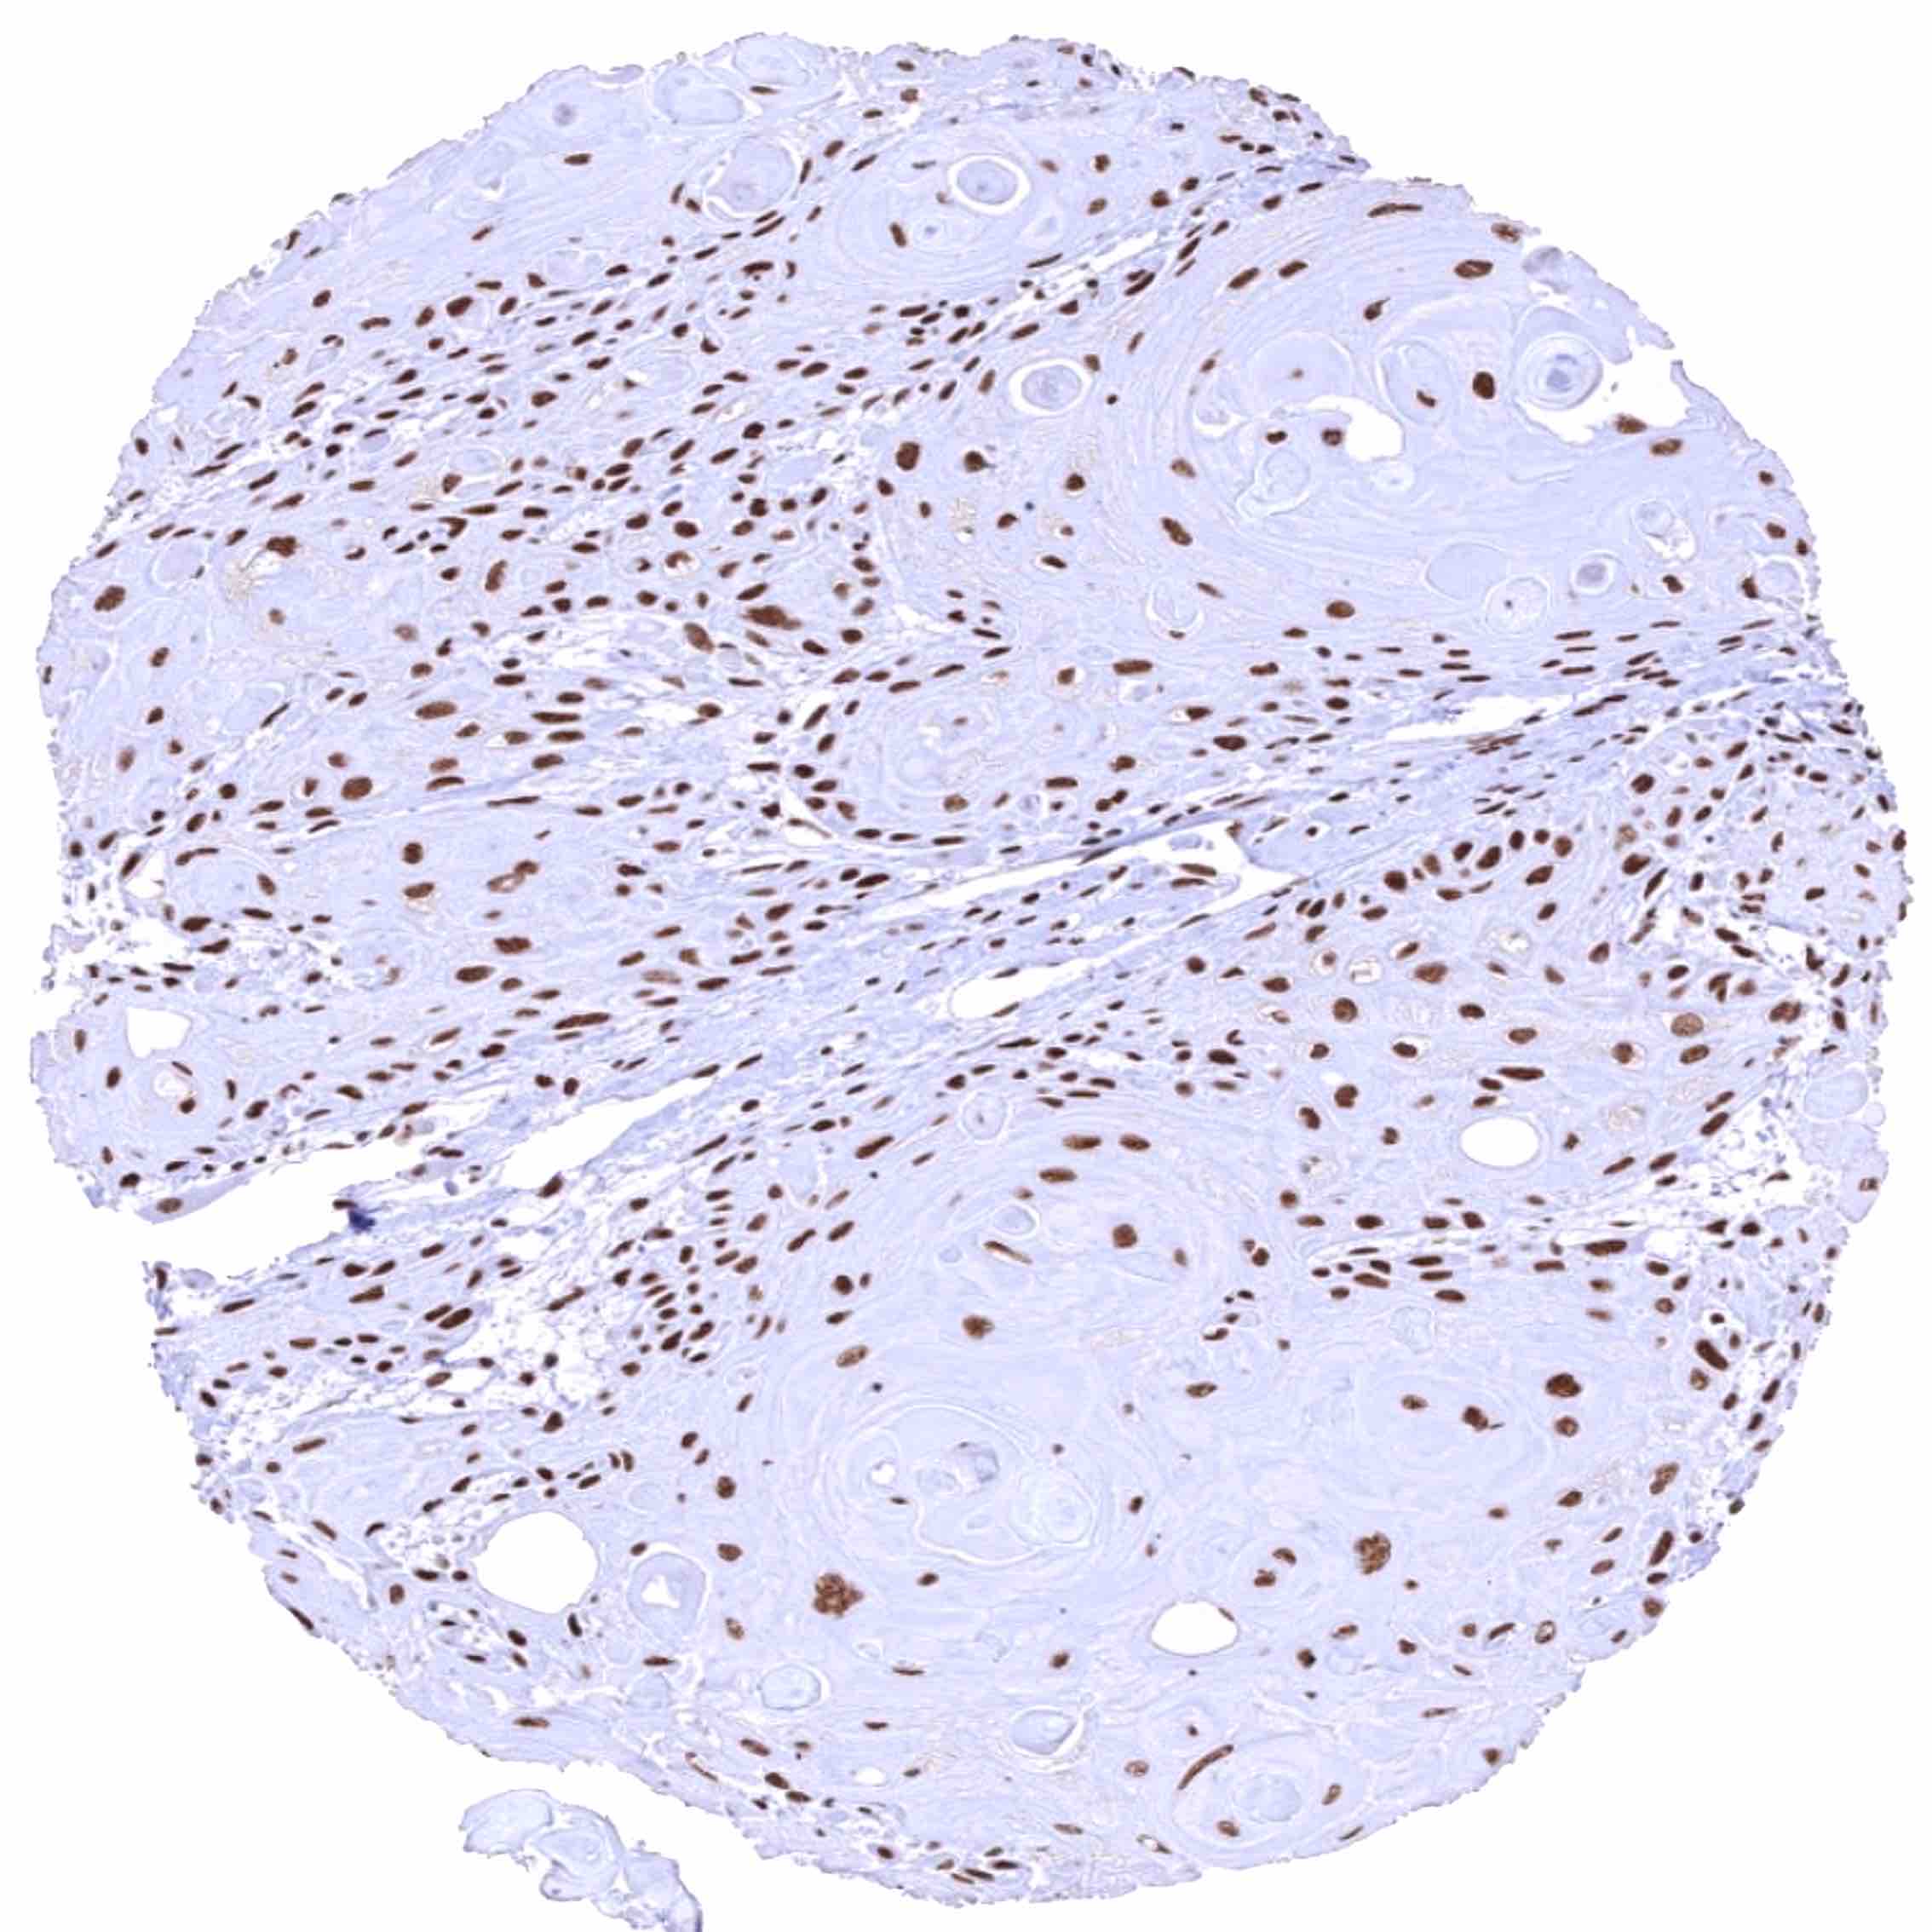

Oral cavity – Well differentiated squamous cell carcinoma with strong BRD4 immunostaining of tumor cells.